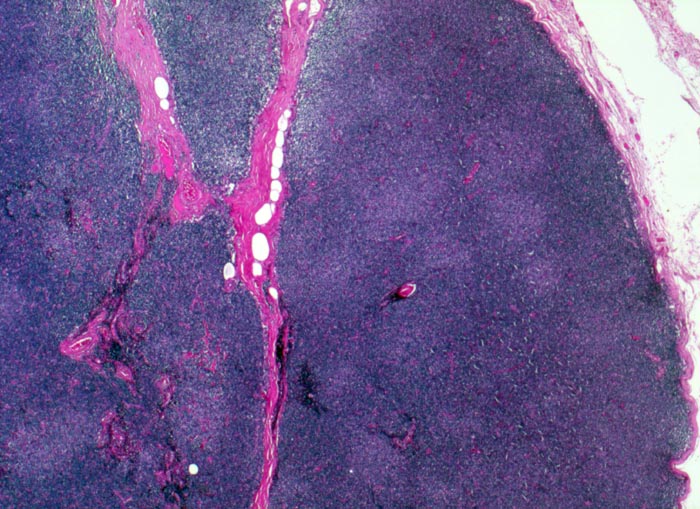

PathoPic – image database / PathoPic ID 3030 - Chronische lymphatische Leukämie vom B-Zell Typ

Chronische lymphatische Leukämie vom B-Zell Typ

Diffuse Infiltration des Lymphknotens durch ein kleinzelliges Lymphom mit Zerstörung der Lymphknotenarchitektur. Die hellen rundlichen Areale entsprechen Pseudofollikeln, die typisch sind für die CLL.

Immunhistochemisch Positivität für den B Zell Marker CD20, für CD23, CD43, CD5. Negativ für Cyclin D1, CD10.

Generalisierte Lymphknotenvergrösserung. Absolute Lymphozytose im peripheren Blut.